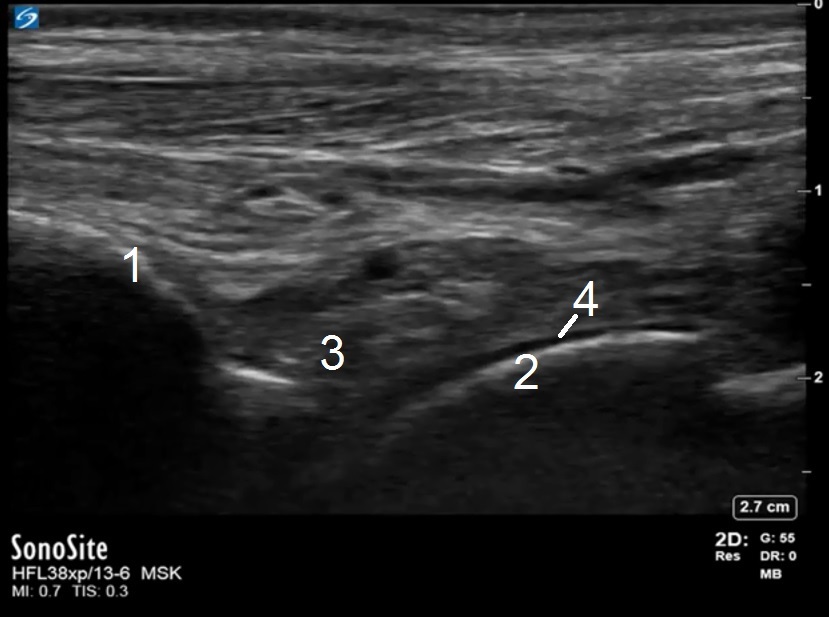

Bild: Fuß und Sprunggelenk, Recessus anterior, Anatomie, lange Achse

1. Tibia

2. Talus

3. Recessus des Tibiotalargelenks

4. Hyaliner Knorpel